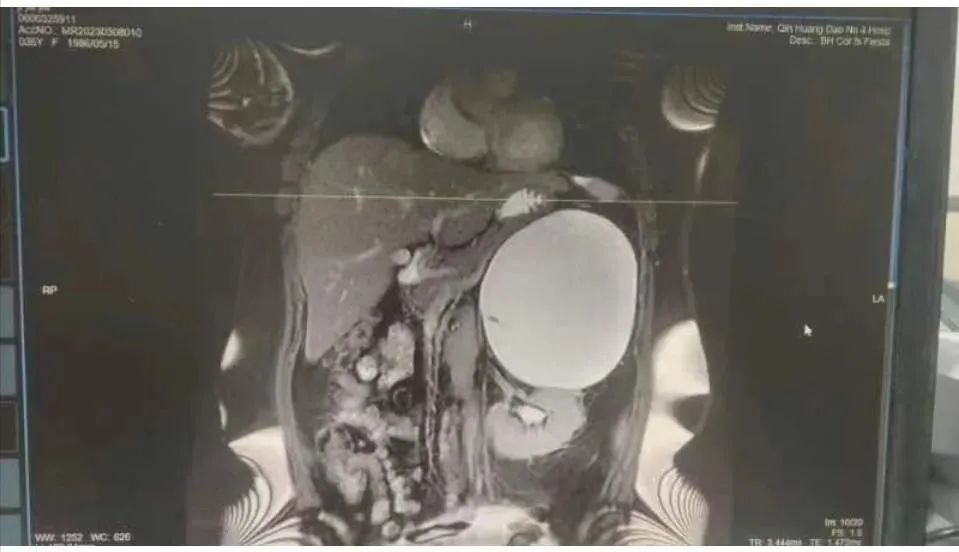

近日,秦皇島市腫瘤醫(yī)院(秦皇島市第四醫(yī)院)外科完成一例巨大腹膜后腫物切除手術(shù)。此前,患者姬女士因咳嗽前往轄區(qū)醫(yī)院就診,經(jīng)CT檢查,發(fā)現(xiàn)脾及左腎之間見一巨大占位,密度不均,約12.3×15.5×9cm3,初步診斷為:腹膜后占位,建議進一步檢查。為了進一步診治,患者出于對市第四醫(yī)院的信任,來到市第四醫(yī)院就診,門診以“腹膜后腫物”收入院。入院后檢查發(fā)現(xiàn)腫物緊鄰膈肌,患者咳嗽考慮為腫物刺激膈肌所致,頻繁劇烈的干性咳嗽嚴重地影響患者的正常生活,亟待改善。